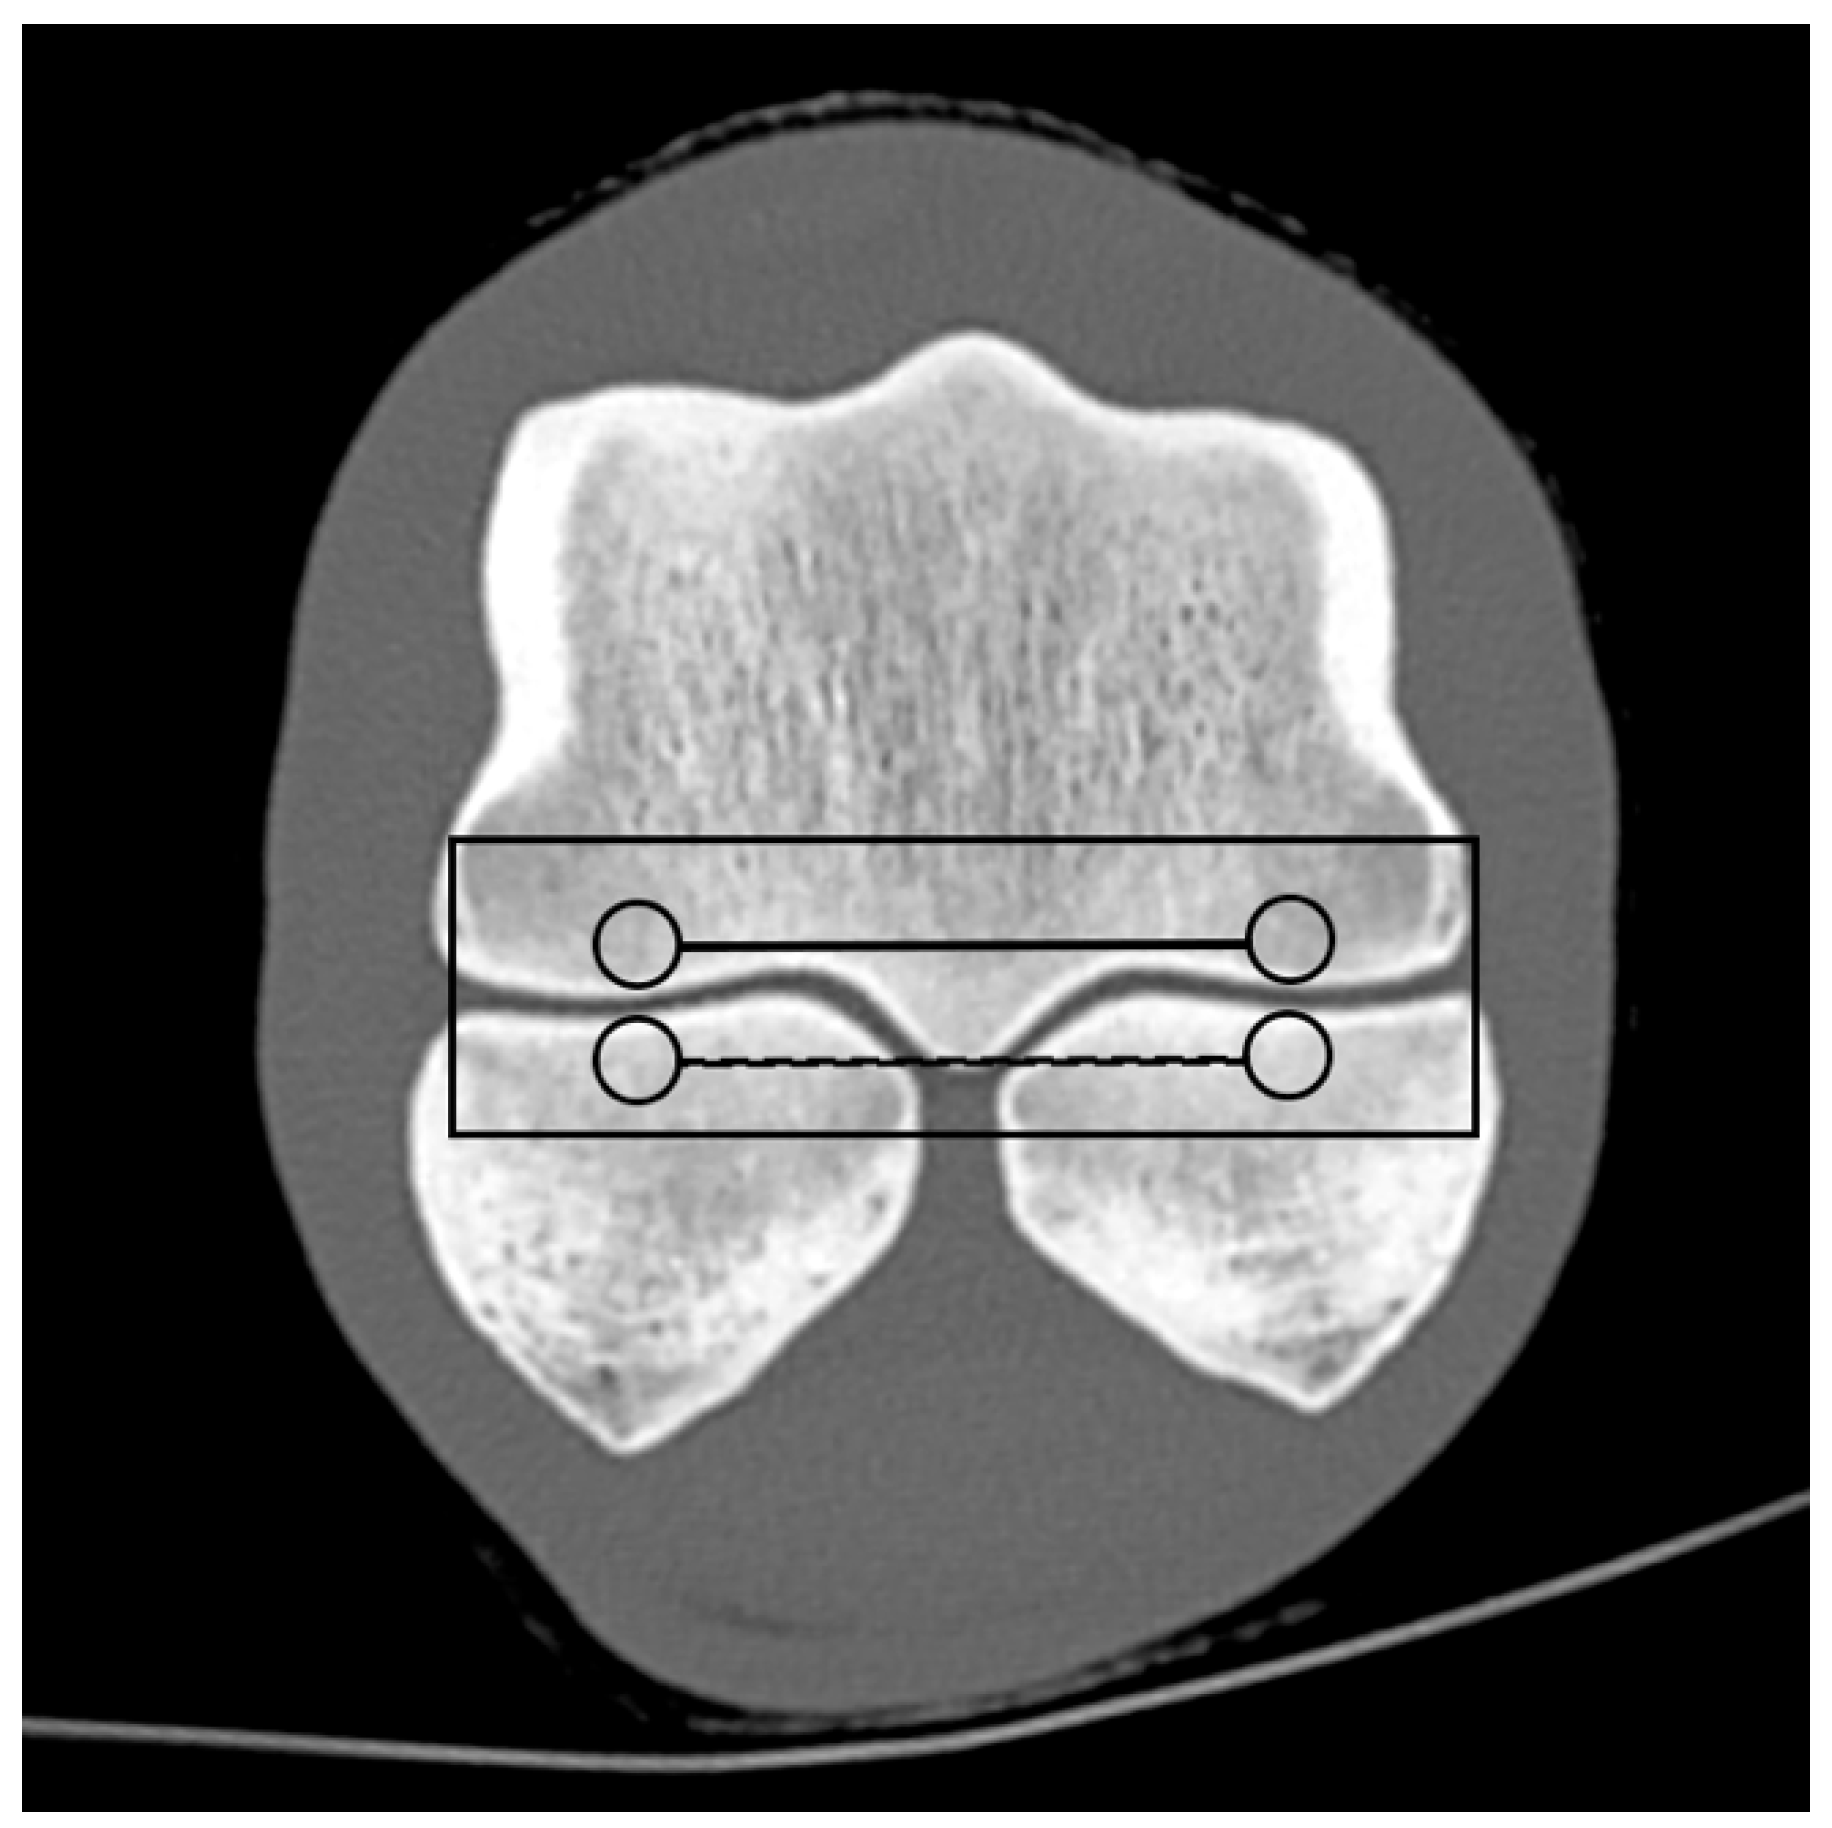

Based on the CT raw data, EAN and ED maps were created from both SSDECT and SBCT images (slice thickness 2 mm), and ROIs were drawn in the virtual monochromatic images (window level 500, window width 2500) using the proprietary software (Raw Data Analysis, CANON Medical and Intellispace Portal 12, Philips Healthcare). Mean EAN/ED values were recorded for each ROI. In total, 29 ROIs and 16 zones were defined for each distal limb. A zone referred to a certain anatomical area, and the mean EAN/ED was calculated from all ROIs included in this area. In the distal aspect of the third metacarpal (MC) and metatarsal (MT) bone, a mid-dorsal image was chosen, and one ROI each was placed in the subchondral bone of the sagittal ridge and the medial and lateral condyle, respectively (dorsal MC/MT zone) (Figure 1). Additionally, a transverse image was chosen at the level of the maximum width of the proximal sesamoid bones (PSB), i.e., at the transition from the distal to the mid-third of the PSBs, and 1 ROI each was placed in the palmar/plantar subchondral bone of the medial and lateral metacarpal/metatarsal condyle (plantar MC/MT zone) and the dorsal subchondral bone of the medial and lateral proximal sesamoid bone (PSB zone) (Figure 2). The mean of all palmar/plantar ROIs in the FJ area (plantar MC/MT and PSB ROIs) represented the palmar/plantar FJ zone (Figure 2). In the first (P1) and second (P2) phalanx, a mid-dorsal image was chosen at the level of the marrow cavity or nutrient foramen, respectively, and in the third phalanx (P3), a dorsal image was chosen parallel to the dorsal surface of the bone at the level of the solar canal. Three ROIs each (medial and lateral fovea, sagittal groove or extensor process) were drawn in the proximal subchondral bone (proximal P1/P2/P3 subchondral zone) and trabecular bone (proximal P1/P2/P3 trabecular zone) distal to the latter in all phalanges (Figure 1 and Figure 3). Larger zones were calculated including all ROIs in the proximal subchondral and trabecular bone of P1, P2 and P3, respectively (proximal epiphyseal P1/P2/P3 zone) (Figure 1 and Figure 3). Moreover, the mean of all dorsal ROIs in the FJ area (distal MC/MT, proximal P1) represented the dorsal FJ zone (Figure 1). A single ROI was also applied to the marrow cavity of P1 (Figure 1). On a mid-dorsal plane of the NB, 3 ROIs were evenly distributed medially, centrally, and laterally within the spongious bone (navicular zone) (Figure 4). All ROIs were of a circular shape with a diameter of 4 mm (smallest ROI possible for both CT units) except for the circular ROI in the marrow cavity of P1, the diameter of which was adapted to the size of the marrow cavity.

Figure 3. Regions of interest (ROIs; circles) and zones (mean EAN calculated from all ROIs included in an anatomical area; lines) in a front second (P2) and third phalanx (P3) on a mid-dorsal monoenergetic image (detector-based spectral computed tomography, Philips): ROIs in the proximal subchondral and trabecular bone of P2/P3 (proximal P2/P3 subchondral/trabecular zone; continuous/dashed lines) and the proximal epiphyseal P2/3 zone (continuous rectangular line).